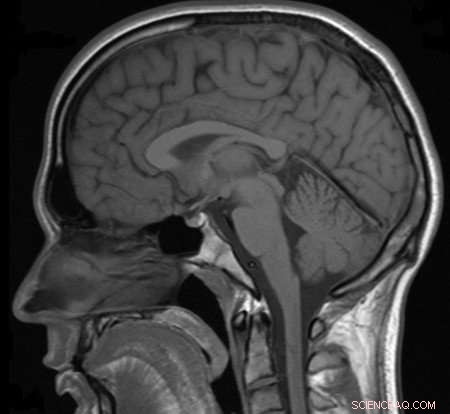

An MRI scan of the head. Credit: Helmut Januschka, CC-BY-SA-3.0

Millions of magnetic resonance imaging (MRI) scans are performed each year to diagnose health conditions and perform biomedical research. The different tissues in our bodies react to magnetic fields in varied ways, allowing images of our anatomy to be generated. But there are limits to the resolution of these images—generally, doctors can see details of organs as small as a half millimeter in size but not much smaller. Based on what the doctors see, they try to infer what is happening to cells in the tissue.